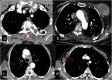

Hydatid cyst caused by the larval form of Echinococcus is a worldwide zoonosis. The lungs and liver are the most common sites involved. While the lung parenchyma is the most common site within the thorax, it may develop in any extrapulmonary region including the pleural cavity, fissures, mediastinum, heart, vascular structures, chest wall, and diaphragm. Imaging plays a pivotal role not only in the diagnosis of hydatid cyst, but also in the visualization of the extent of involvement and complications. The aim of this pictorial review was to comprehensively describe the imaging findings of thoracic hydatid cyst including pulmonary and very unusual extrapulmonary involvements. An outline is also given for the findings of complications and differential diagnosis of thoracic hydatid cyst.